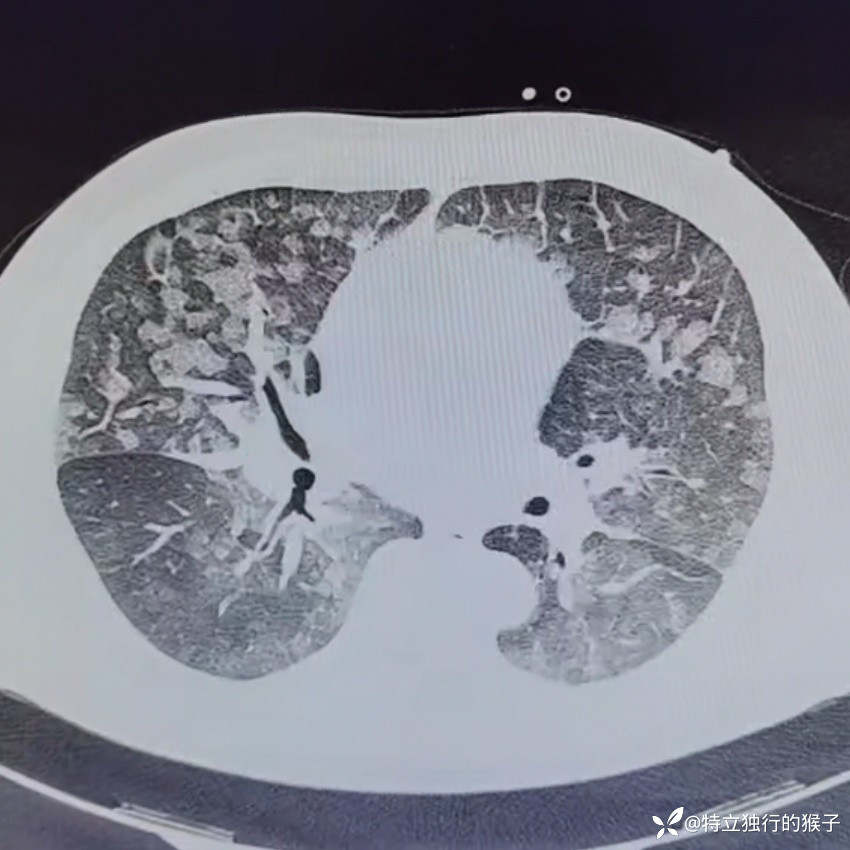

30y/M,1天前出现咳嗽,咳粉色泡沫痰,胸痛,胸闷气急,无发热。既往有肾炎病史。

查体:SpO2 85%,血压169/125mmHg,神志清,呼吸急促,口唇紫绀,两肺呼吸音粗,两肺闻及弥漫湿啰音,双下肢无水肿。

cTnI 0.66ng/ml;NT-proBNP 4183ng/ml。D-Dimer 0.17mg/l;肌酐271umol/L,BUN15mmol/L。